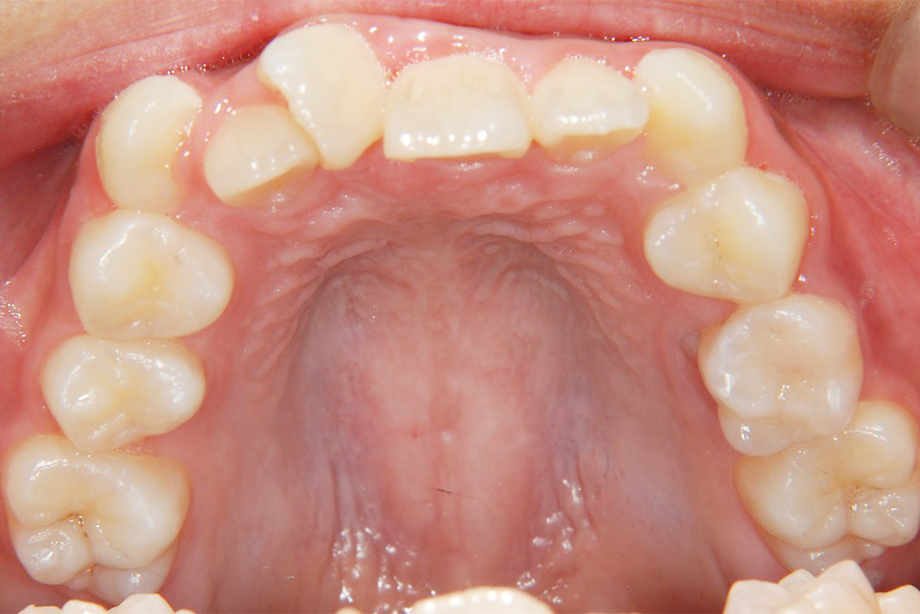

第Ⅰ期治療

乳歯、もしくは乳歯と永久歯が混ざっている時期の治療です。歯の治療というよりも、顎の骨の成長を促したり、歯並びに影響を与える筋機能の訓練などを行います。

- 矯正後